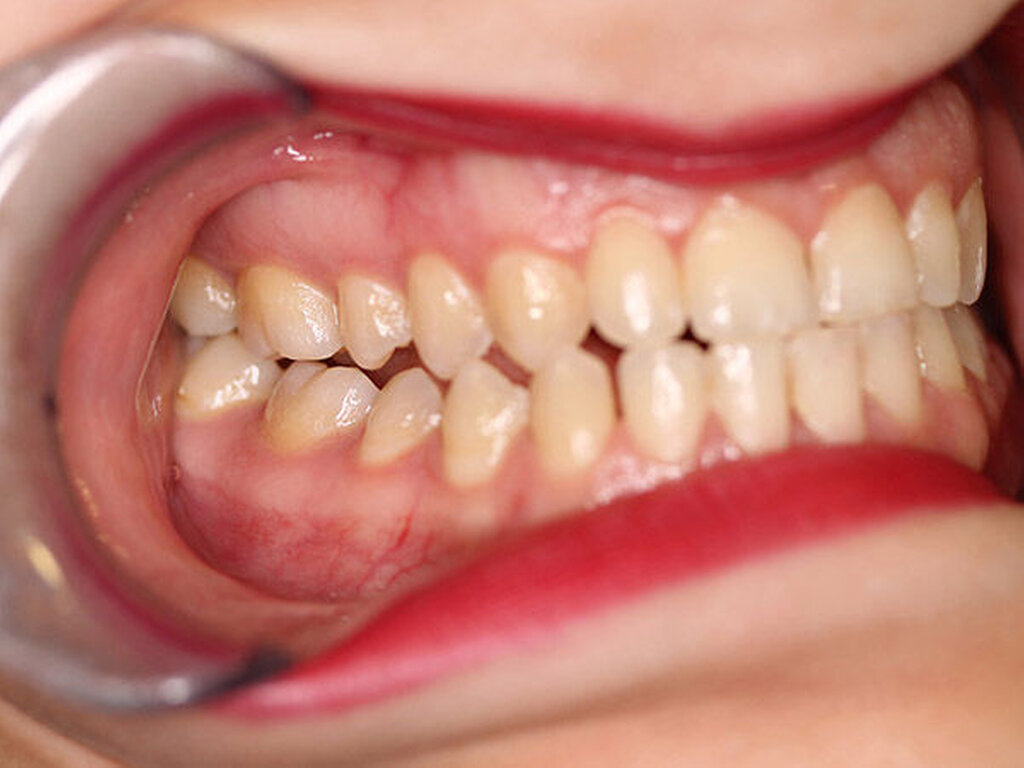

Intraoral fand sich eine Mesialbisslage von einer halben Prämolarenbreite im Seitenzahnbereich beidseits. Ein Kontakt bestand regio 16/47 mit Nonokklusion der restlichen ipsilateralen Eck- und Seitenzahnregion (Abbildung 2). In regio 11/41 fand sich eine Kreuzbisssituation, in regio 21/31 eine Kopfbisssituation. Die Unterkiefermittellinie war interessanterweise um 3 bis 4 mm nach rechts verschoben, das knöcherne Kinn hingegen nach links. Weitere faziale Fehlbildungen lagen nicht vor.

Die Patientin wurde in unsere ambulante Nachsorge entlassen. Geplant wurde eine Knochenszintigrafie zwölf Monate nach der Operation. Bei der letztmaligen ambulanten Vorstellung zwei Jahre postoperativ zeigte sich ein stabiler Befund. Die Unterkieferbeweglichkeit war uneingeschränkt, ein Kiefergelenksknacken rechts im terminalen Drittel der Mundöffnung hör- und spürbar. Beschwerden hatte die Patientin dadurch nicht. Die Okklusion war im Vergleich zum präoperativen Befund verbessert und stabil (Abbildung 6). In der Knochenszintigrafie konnte eine geringe Knochenstoffwechselsteigerung in Projektion auf das rechte Kiefergelenk festgestellt werden, dieses war vereinbar mit einem vermehrten postoperativen knöchernen Umbau.